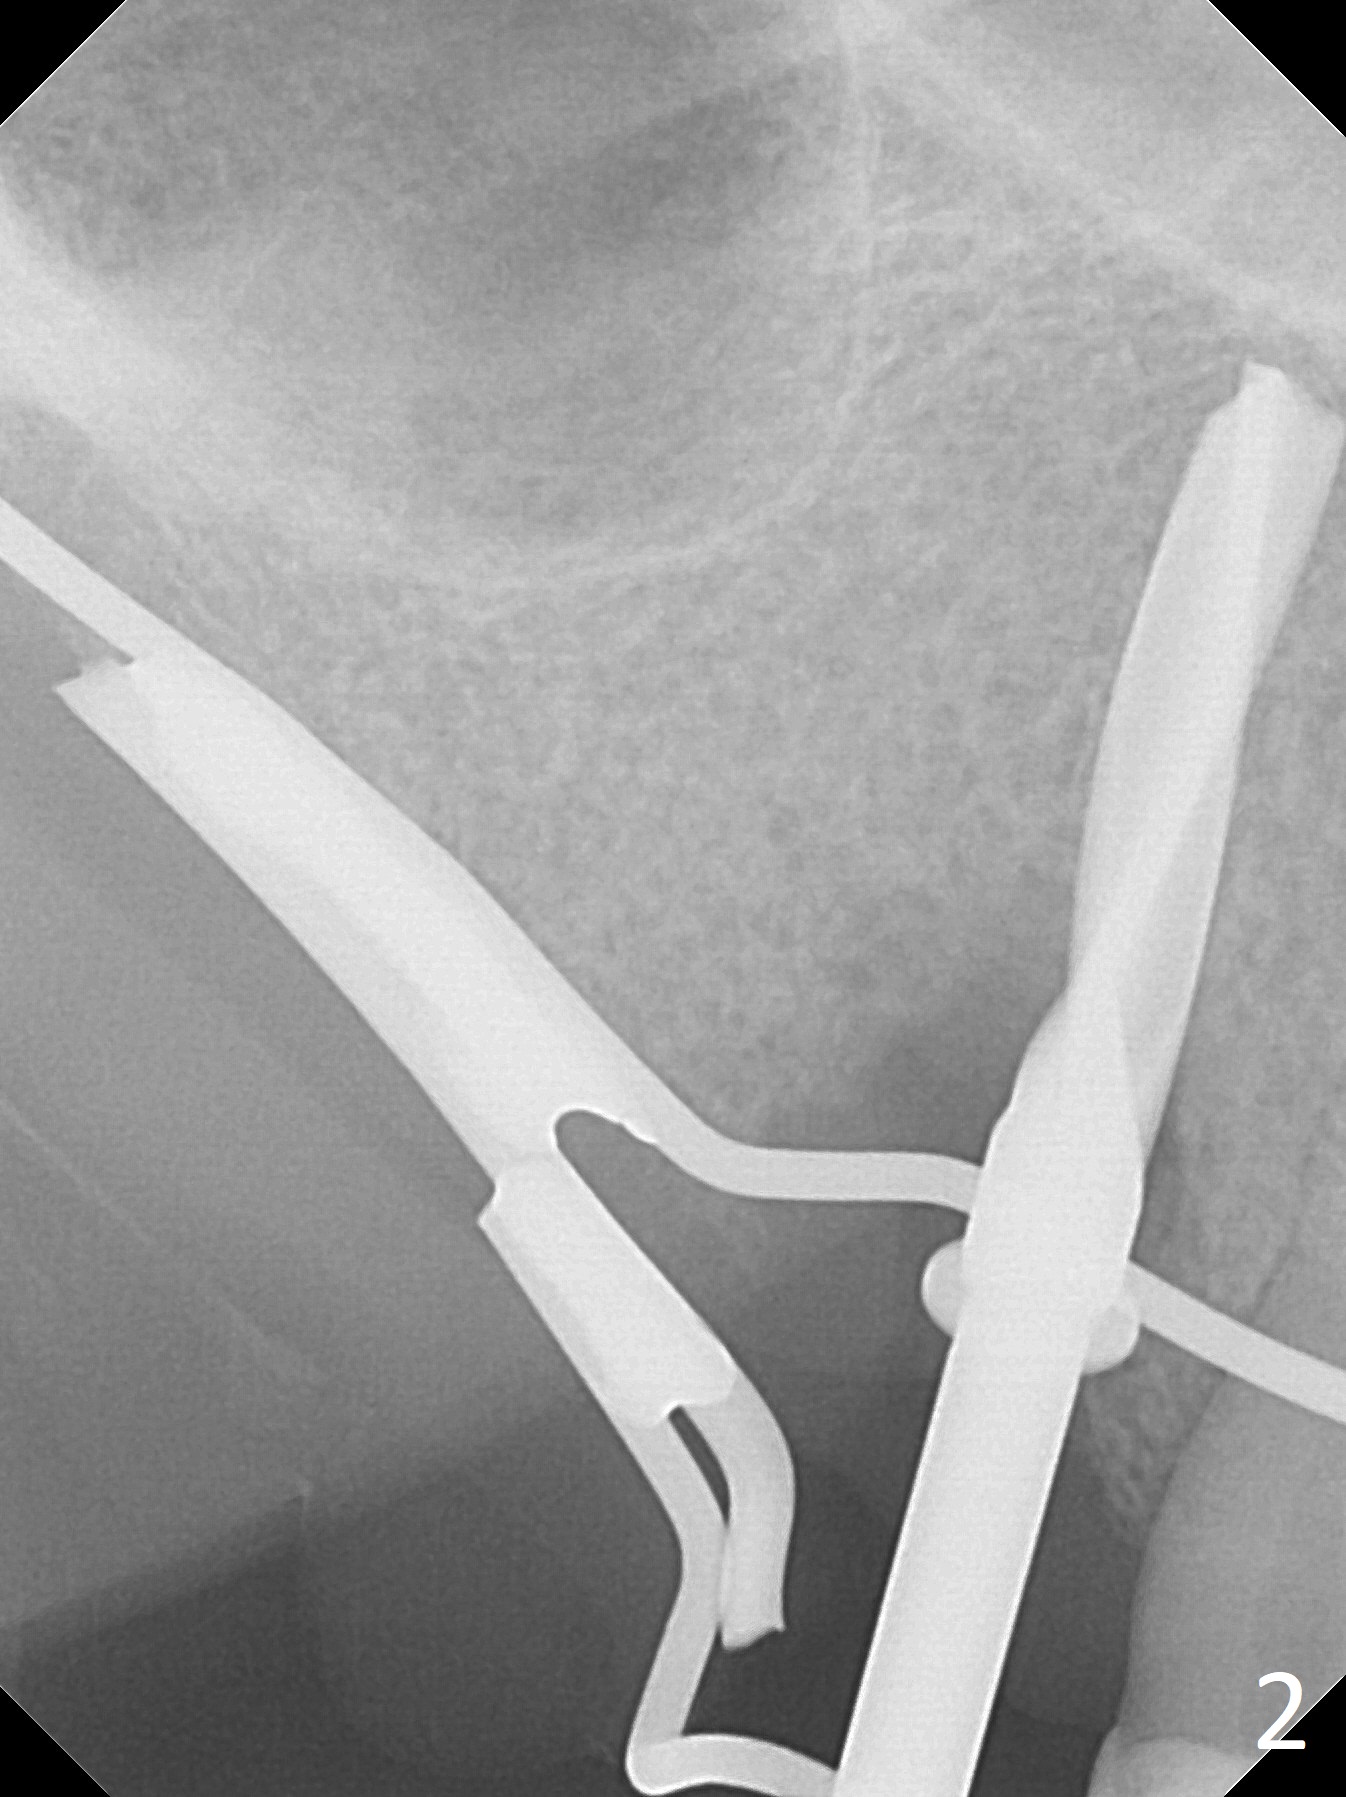

Extraction of the tooth #5 with mobility III reveals no buccal plate and low palatal plate.  Osteotomy starts as palatal as possible (Fig.1).  The bone density is low.  After use of 2.7 mm drill (Fig.2), a 3 mm drill can be inserted into the osteotomy without resistance.  A 4x16 mm implant is placed with insertion torque <30 Ncm.  When an abutment is placed, the implant is found to have been placed distal.   The implant is untorqued for change in trajectory.  When a 4.5x7(5) mm abutment is placed, the abutment turns with the underlying implant (Fig.3).  The former is kept to be turned with a hand driver until the latter is unable to turn.  Following placement of allograft (Fi.g3,4 *), a mini-provisional is fabricated to retain the bone graft and at the same time not to be interfered with when a flipper is in and out.  The bone graft in the former socket gap appears to have integrated into the native one 4.5 months postop (Fig.5).